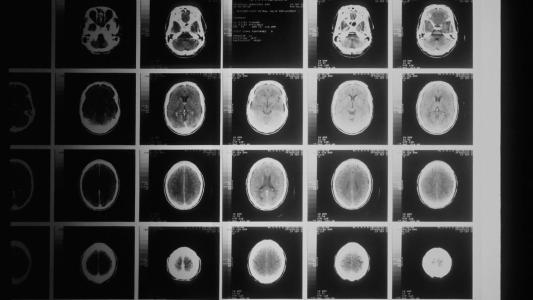

3D-printing the brain’s blood vessels with silicone could personalize neurosurgery

3D printing could make blood vessel replicas with the soft feel and the structural accuracy surgeons need.